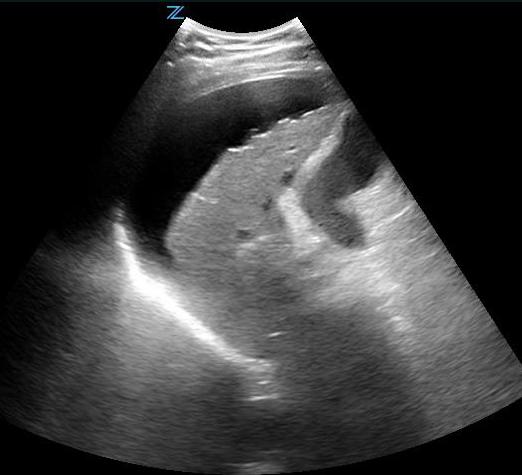

- Right Coronal and Intercostal Oblique Views:

- The easiest abdominal view to obtain is the view of Morison’s pouch. (Ill. 4)

- Place the probe in the mid-axillary line at about the 8th to 11th intercostal space with the transducer indicator pointed cephalad. (Fig. 4)

- This gives a coronal view of the interface between the liver and kidney. (Fig. 5) It is important to follow the lower edge of the liver caudally until a good view of the liver tip is obtained as fluid will often collect there first. (Video 4)

- Free fluid is usually seen in Morison’s pouch or along the lower edge of the liver and around the lower tip of the liver. (Figure 5, Videos 5-8)

- Figure 5. Small amount of free fluid Morison’s pouch view